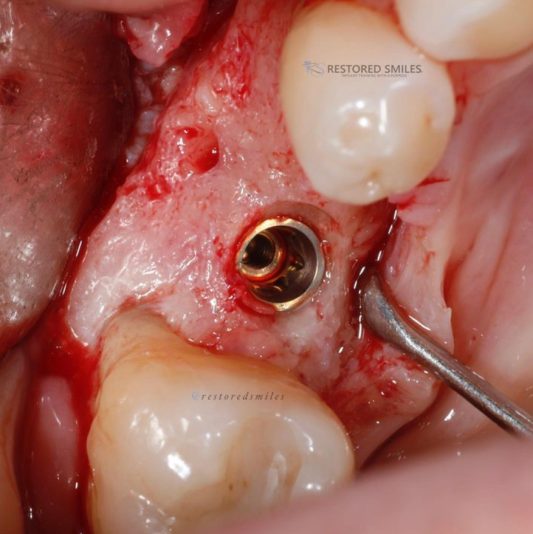

• Looks good, right?!? Not once you see the cbct and create a larger full thickness flap. What would you do here? What are your options? This happened during one of our live surgery courses. Please leave a comment below on what you would do and a couple options we may have. After I recieve several comments I will post a follow up post next week…

Read more

• implant position looks too buccal to me in this photo. i’d remove and start a new osteotomy and sink the implant to the level of the lingual bone